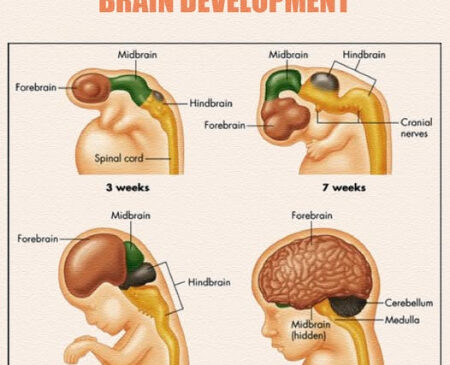

رشد جنین یکی از پیچیدهترین فرآیندهای بیولوژیکی است. این فرآیند تحت تأثیر عوامل مختلفی مانند تغذیه مادر، وضعیت سلامتی مادر، مشکلات ژنتیکی، و شرایط محیطی قرار دارد. مشکلات رشد جنین به دلایل مختلف میتواند ایجاد شود که برخی از مهمترین این دلایل عبارتند از:

یکی از امکانات جالب هوش مصنوعی، توانایی آن در تحلیل دادههای ژنتیکی است. با استفاده از این فناوری، پزشکان میتوانند اطلاعات ژنتیکی والدین را بررسی کرده و پیشبینیهایی درباره مشکلات ژنتیکی جنین مانند نقصهای کروموزومی (مثل سندرم داون) انجام دهند. این شبیهسازیها میتوانند به تشخیص بیماریها در مراحل ابتداییتر کمک کنند.